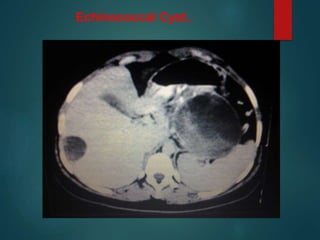

Echinococcal Cyst..

• #30 It is unusual for an echinococcal cyst to be located in the peritoneum. It favours the liver spleen n kidney over the peritoneum. Here we see cyst in peritoneum and in LIVER, Notice the daughter cysts as small dark lesions within the large peritoneal cyst.calcified rim is a favouring features.